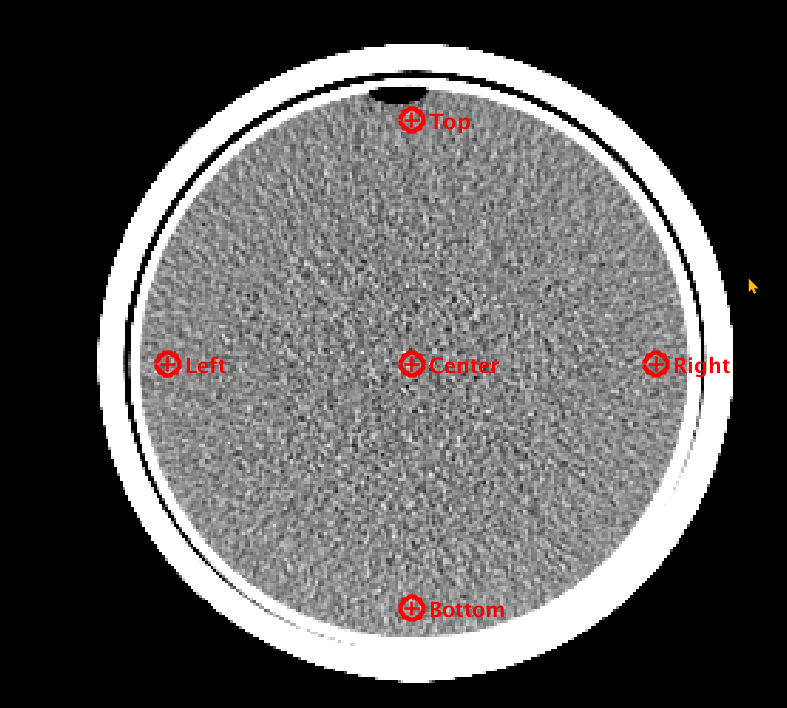

Uniformity

The uniformity module measures the mean and standard deviations of 50mm2 ROI’s located in the center of the phantom ad at the four cardinal angles towards the edges of the phantom. Each edge ROI’s mean value is compared against the center ROI. The ROI with the maximum deviation is identified.